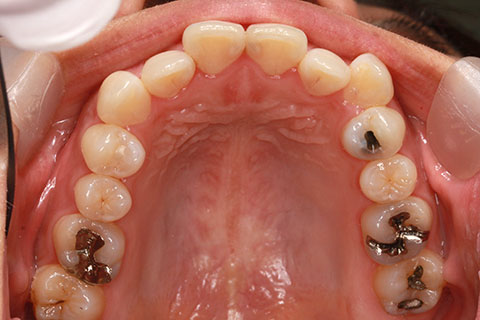

治療前